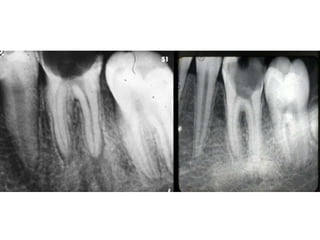

• Large open cavity with direct access to the

pulp chamber,

• Widening of pdl space

• Discontinuity of lamina dura

• Widening of lamina dura

• The tooth with necrotic pulp may exhibit only

slight periradicular change, periradicular

bony lesion may accompany the necrotic pulp

Appear normal except for widening of PDL

space.

• Large opencavity with direct access to the pulp chamber, • Widening of pdl space • Discontinuity of lamina dura • Widening of lamina dura

• The toothwith necrotic pulp may exhibit only slight periradicular change, periradicular bony lesion may accompany the necrotic pulp

Appear normal exceptfor widening of PDL space.